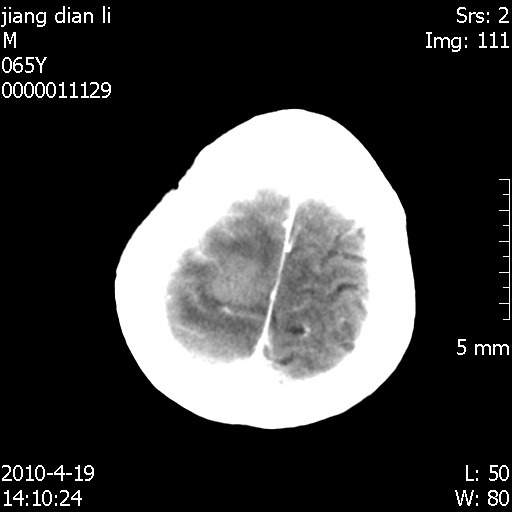

老年男性,突发左下肢无力1天,其余有价值的检查都没有。平扫ct值大约60hu,增强后ct值没什么改变,请大家讨论一下这个病例是什么?说明诊断理由。

左小脑、右大脑顶叶多发圆形高密度病灶,其周环状低密度影。考虑多发脑出血。隔期观察。

至于是出血还是微小钙化所致的高密度无法考证,三个都出血也不是一点都不可能,同一种组织学类型的肿瘤受到同一个外来的因素影响后会表现出相同的病理变化。说实在的,我本身支持转移瘤的,就是想不通为什么不强化?我认为单纯脑出血的边缘不会那么光滑,并且那也不是出血的常见部位,多发也不常见。

刚刚复习了转移瘤的不典型ct征象,有4条,分享给大家:

1、高密度灶:多为瘤内有较多沙粒体钙化所致,而不是出血,ct值可高达95hu;

2、无强化;

3、无水肿;

4、无占位效应。